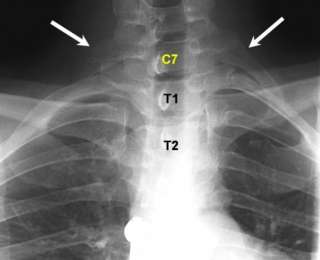

Дополнительные ребра

«Лишние» ребра чаще обнаруживаются у прекрасной половины человечества. Видимо, по этой причине некоторые люди верят, что женщины рождаются с большим числом ребер, чем мужчины, но на самом деле это не так.

Такие ребра еще называют шейными, так как они локализуются в шейном отделе позвоночника. Их размеры у разных людей неодинаковы — у кого-то они представляют собой небольшие наросты, в то время как у других являются полноценными ребрами.

Эти ребра в большинстве случаев никак не влияют на здоровье и самочувствие человека, но порой они достигают внушительных размеров и могут причинять дискомфорт.